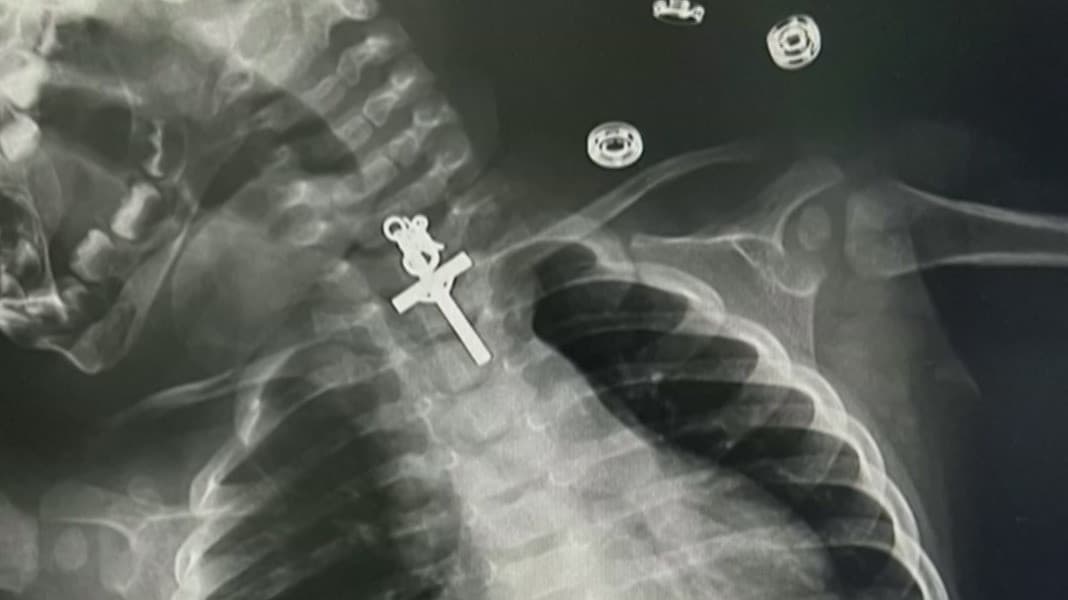

Bebé hispana de 10 meses se traga un crucifijo por accidente: tuvo que ser operada de emergencia

La madre llevó a la menor al hospital y los médicos tuvieron que realizarle una cirugía de emergencia que duró aproximadamente seis horas. Al respecto, el Dr. Juan explica cómo fue el procedimiento al que tuvo que someterse la bebé y qué hacer en casa para que este tipo de sucesos no ocurran. Más información en Univision Noticias.